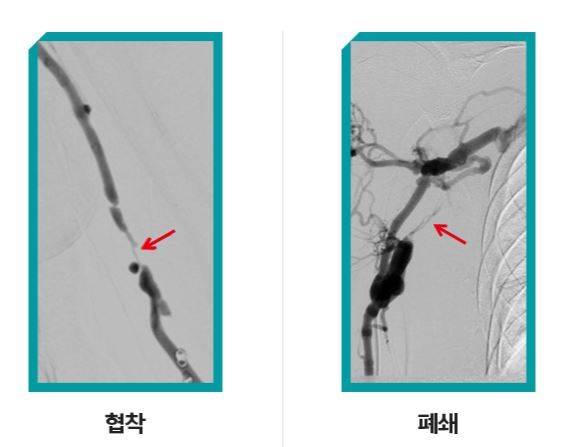

이렇게 만들어 놓은 투석혈관은 시간이 지날수록 필연적으로 좁아지거나 막히게 된다. 주삿바늘을 반복적으로 꽂았다 빼면서 굳은살이 생기고, 만성콩팥병 특성상 혈관 속 노폐물이 쌓이기 쉽다. 이렇기 때문에 투석혈관이 막히는 것을 최대한 예방하기 위해 철저한 사후관리와 검진이 필수다.

만약 투석혈관이 막히거나 좁아져 간다면 인터벤션 치료인 투석혈관 재개통술 등을 통해 혈관을 개통해 다시 사용할 수 있다.

배재익 대표원장은 “혈관개통술은 여러 번 다시 개통해 사용할 수 있고 시술 후에 바로 투석이 가능하다”며 “하지만 혈관 상태가 좋지 않거나 너무 오래 방치된 혈관은 재개통술 만으로는 어려울 수 있어 수술과 시술을 융합한 치료 또는 새로운 투석혈관을 만들어야할 수 있다”며 정기적인 혈관 점검을 당부했다.